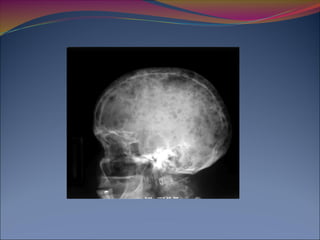

14 Rayos X:

Cráneo (AP y Lat)

80% de los pacientes tienen alteraciones en las Rx

Blood. 2011 May 5;117(18):4701-5.

14 Rayos X: Cráneo(AP y Lat) Columna Cervical (AP y Lat) Columna Torácica (AP y Lat) Columna Lumbar (AP y Lat) Fémur (AP y Lat) Húmero (AP y Lat) Tórax (PA) Pelvis (PA) 80% de los pacientes tienen alteraciones en las Rx Blood. 2011 May 5;117(18):4701-5.